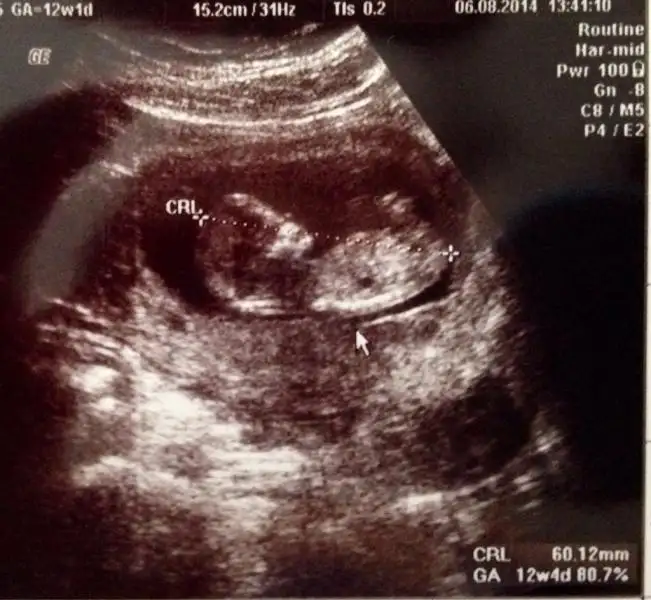

Güzel annişleeeer nasılsınız? Biz bugün ikili teste girdik şükür ölçümlerimiz güzel çıktı. Ana doktorumuz anca 16. haftada söylicem cinsiyet dedi.

Ben de burdan size soriyim dedim usta gözler bi göz atsanız benim limonuma pek bi seviniriz:) 12+4 görünüyoruz burda :)

Hepinize sağlıklı hamişlikler 😘